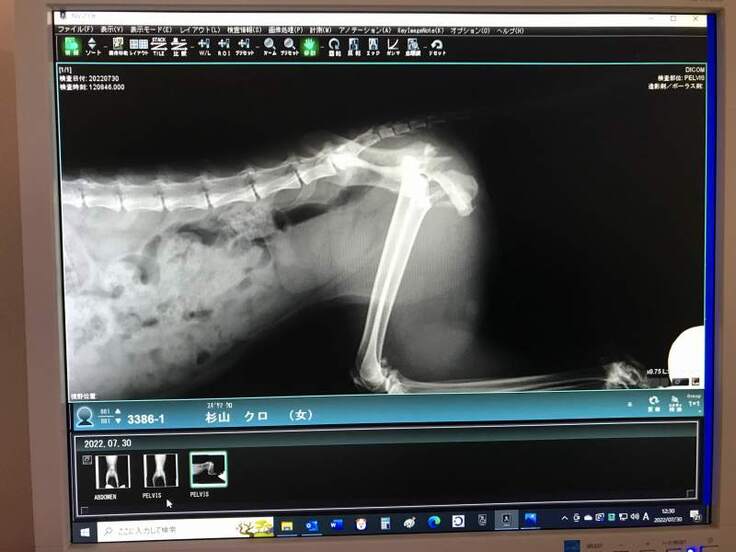

脚が立たないようなので仔猫2匹とクロちゃんを一緒に保護して動物病院で診察してもらうと、骨盤骨折していました。

初診のレントゲンでは骨盤の左側が骨折という診断で手術を受けましたが、手術後のレントゲンで右側も骨折していて、粉砕骨折しているという結果でした。

2回目の手術を受けて今はリハビリ中です。

交通事故に遭ったのだと思いますが、骨盤骨折して立てない動かない脚を前脚だけで引き摺って仔猫の元に帰ろうともがいて頑張って家の前まで帰って来ていたクロちゃん、なんとかうまく骨がつながって普通に歩いて走ってジャンプできるようになって欲しいと思います。

長く待てないので、既に骨盤骨折の手術を2回受けました。

今は徐々に回復してヨタヨタしながらでも歩けるようになっていてリハビリ中です。

定期的に通院して経過を診てもらいます。